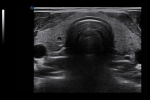

Crystal Purity Transducer

Equipped with the crystal purity transducer, Apogee 5800 Ace conducts superb scanning on cardiac diseases such as CHD (congenital heart disease).

TEE

As a minimally invasive diagnostic way and real-time cardiac imaging device, TEE (Transesophageal echocardiogram) ultrasound is capable of providing additional diagnostic information.